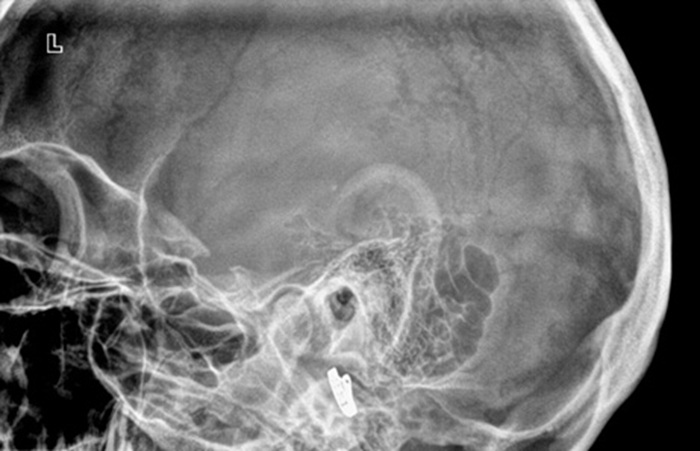

Результатом обследования в проекции по Шуллеру является информативный снимок. По снимку врач может выявить доброкачественные опухоли и злокачественные новообразования в височной области. Также по снимку можно определить степень сложности переломов и ушибов височной области, детально изучить структуры костей и тканей в различных проекциях. Кроме того, снимок позволяет отслеживать ход лечения при заболеваниях уха.